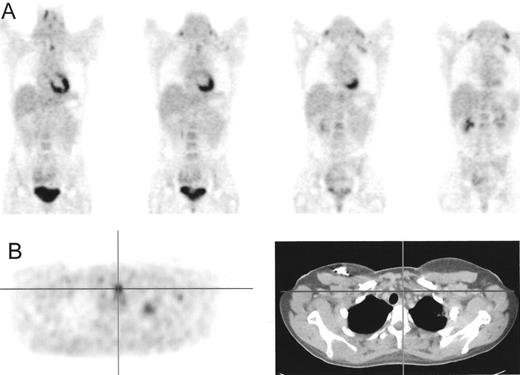

Patient with Hodgkin’s lympoma, nodular sclerosis, stage IIB based on conventional imaging modalities (computed tomography [CT] and iliac crest biopsy).

Positron emission tomography (PET) also showed increased fluorodeoxyglucose (FDG) uptake in the lumbar spine suspected for bone involvement (A) upgrading this patient to stage IVB. PET after 4 cycles of ABVD (Adriamycin®, bleomycin, vinblastine, dacarbazine), (B) only showed increased FDG uptake in bone marrow secondary to marrow regeneration. The hot spot in the spine has become cold representing replacement of the bone marrow by nonviable tumor tissue.